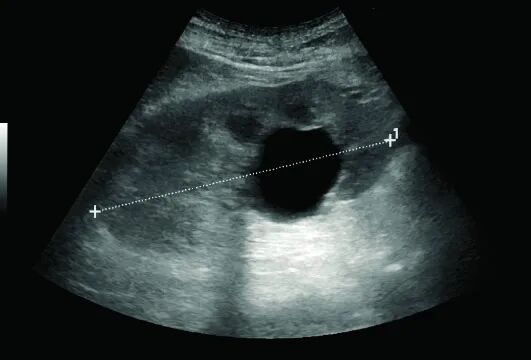

肾囊肿与肾肿瘤

肾囊肿

肾囊肿是常见良性病变,超声下表现为圆形或类圆形的无回声区,边界清晰,后方回声增强。简单囊肿通常无需处理,但复杂囊肿可能需要进一步检查或随访。